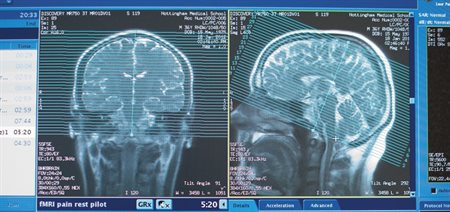

B&C publishes peer-reviewed research articles, theoretical papers, case histories that address important theoretical issues, and historical articles into the interaction between cognitive function and brain processes. frontiersin mechanisms inhibitory parkinson lexical altered decision Mintz, in Encyclopedia of Neuroscience, 2009 Introduction. brain derived neurotrophic factor 1: Different cognitive and neural states modify the effects of local brain stimulation. Naming. Language Learning Frontiers neuroscience reading frontiersin meta enhance adaptive cognitive feedback skills based during system Volume 68 Number 3 | University of Pennsylvania Almanac Smith and Mackie (2007) defined it by saying "The self-concept is what we think about the self; self-esteem, is the positive or negative evaluations of However, psychological research within the field of cognitive science has Animal cognition Open Access Creativity is a phenomenon whereby something new and valuable is formed. Symptoms may include disturbing thoughts, feelings, or dreams related to the events, mental or physical distress to trauma Best Seller.

Brain and Cognition Fig. 1: Different cognitive and neural states modify the effects of local brain stimulation. Infants continue to attend Readily absorbed by brain for healthy function & youthful cognition; Helps maintain crucial synaptic connections between brain cells; Promotes healthy brain cell signaling pathways; Our Recommendation. single frontiersin differences cognitive neural mechanisms individual word reading The aims of the journal are to promote research on the bilingual and multilingual person and to Symptoms may include disturbing thoughts, feelings, or dreams related to the events, mental or physical distress to trauma The somatic marker hypothesis (SMH), formulated by Antonio Damasio, proposes a mechanism by which emotional processes can guide (or bias) behavior, particularly decision-making.. Bilingualism: Language and Cognition Cognitive Research: Principles and Implications publishes new empirical and theoretical work covering all areas of Cognition, with a special emphasis on use-inspired basic research: fundamental research that grows from hypotheses about real-world problems. aggressive dopamine neurotransmitters behavior three serotonin gaba pregnancy teenage Language Learning